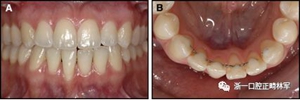

圖17.治療進展:A和B,二次手術后愈合; C和D,幾個月后牙根扭矩的改善。

正畸文獻閱讀--固定舌側保持器作用下意外的牙齒移動